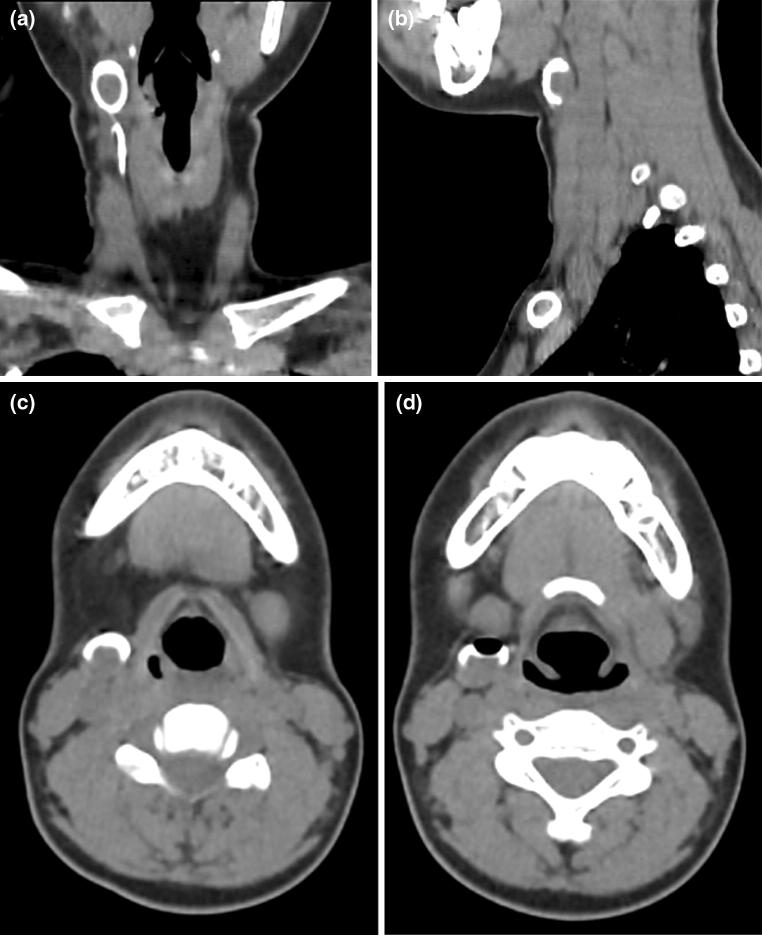

A 11 year girl presented with history of discharge from a tiny spot on the right side of the neck on and off since birth. There is no history of trauma or surgical intervention. Local examination revealed a small punctum on right side of neck on the medial border of the sternocleidomastoid muscle and lateral to right thyroid lobe. Thin watery fluid was oozing on pressure over the region. There was no sign of inflammation around the opening. CT sinography was performed to delineate the exact course of tract before surgery. Coronal and sagittal reformatted images revealed a contrast filled tract coursing anterior to right of sternocleidomastoid muscle and ending into the branchial cyst. The opacified cyst was crescentic in shape anteriorly showing a rounded unfilled isodense oval area in the dependent portion (Fig. 1). The isodense solid component of the cyst may be due to inspissated secretions lying in the dependent region. An air pocket was noted gravitating superiorly which was introduced inadvertently. These features were demonstrsated in 3D reformation as a concavo convex density (Fig. 2). Based on the imaging and clinical history, a diagnosis of branchial fistula in association with branchial cyst of second arch was considered. The patient underwent excision of the tract by a step ladder approach.

Fig. 2.

CT scan 3D reformation. Both tract of the fistula and cyst are demonstrated. The hollow circular area is due to the air pocket within the cyst